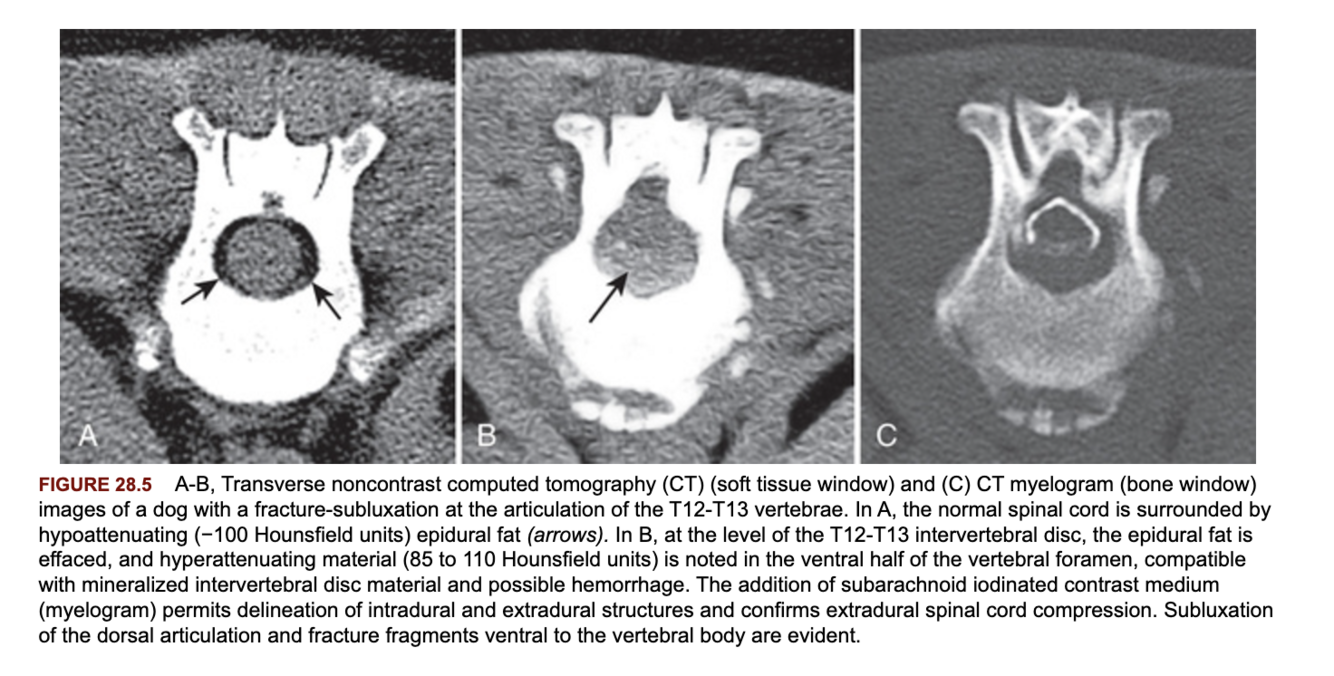

What provides normal contrast within the vertebral canal on CT?

The epidural fat. Loss of the epidural fat can result in loss of contrast. Myelography can be used to overcome this issue.